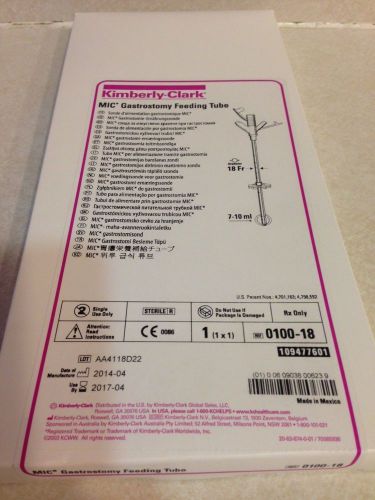

KIMBERLY CLARK MIC* GASTROSTOMY FEEDING TUBE REF:0100-18